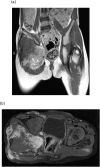

Presentation of cases: Out of 7 pediatric patients, there were 6 (85.7%) males and 1 (14.3%) female patient. The median age was 6 years IQR (5-11) years. Gluteal region was the most common site of disease. Four patients (57.1%) had positive tumor margins while three (42.9%) had negative margins. Out of 7 patients, 4 patients (57.1%) had recurrent disease and they had positive margins. The median Disease Free survival time was 14 months and there was no expiry of patients.